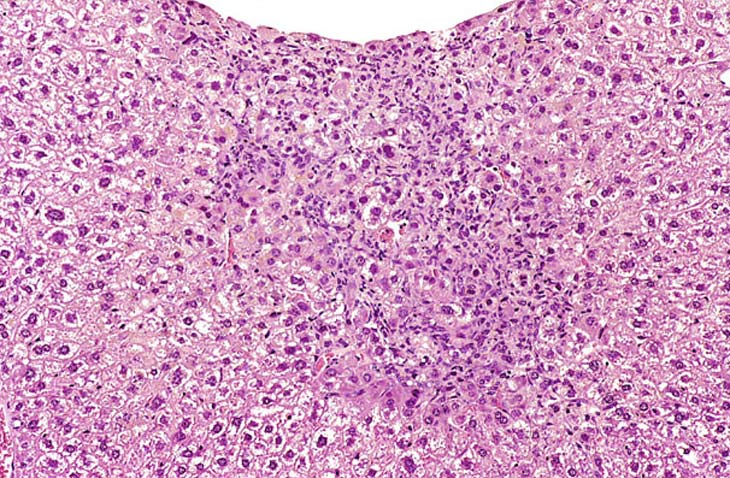

This change was originally diagnosed as endothelial cell proliferation. Based on the H&E stained sections, it is not possible to definitively identify the proliferating sinusoidal lining cells as endothelial cells but some have cytomorphological features consistent with endothelial cells. Low and high magnifications of endothelial cell hyperplasia.